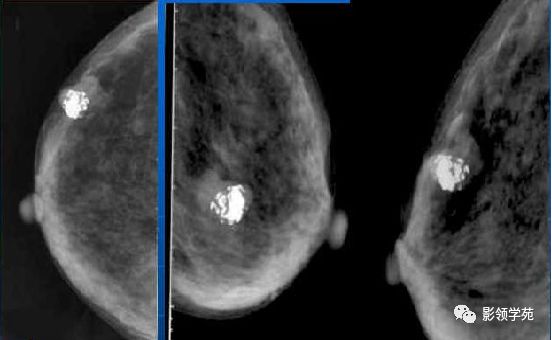

乳腺钙化的鉴别诊断与分级